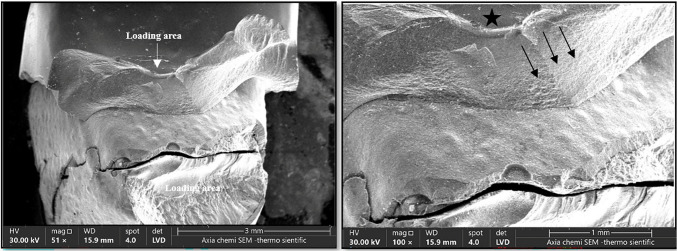

评估和比较氧化锆和二硅酸锂两种陶瓷冠在两种边缘设计(垂直和水平)下的疲劳后抗断裂性能。选取正畸科采集的健康人前磨牙40颗,按陶瓷材料类型随机分为两组(n = 20): A组为二硅酸锂组,B组为单片氧化锆组。每组根据边缘设计进一步细分为两个亚组(n = 10):羽毛边缘(1)和肩部(2)准备设计。经数字扫描和设计后,用自粘树脂粘接冠。每个组件在水中进行循环加载(1,000,000次,100 N, 1 Hz),然后进行轴向压缩加载直到断裂。通过扫描电镜断口分析,分析了试样的破坏模式。B1亚组(垂直制备的氧化锆:3129 N)的断裂抗力均值最高,B2亚组(水平制备的氧化锆:2616 N)次之,而二硅酸锂冠的断裂抗力均值较低(A1组:1880 N, A2组:1512 N)。单因素方差分析显示,两种冠材料的抗折性差异有统计学意义(p 0.05)。氧化锆冠和二硅酸锂冠的断裂强度均超过前磨牙区域的咬合力水平,支持在后牙区域使用保守的羽边制备方法。

To assess and compare the post-fatigue fracture resistance of two types of ceramic crowns, zirconia and lithium-disilicate, when used with two margin designs (vertical and horizontal). Forty sound human premolar teeth collected from the orthodontic department were divided randomly into two main groups according to the type of ceramic material (n = 20): Group A: Lithium-disilicate and Group B: Monolithic zirconia. Each group was further subdivided according to the margin design into two subgroups (n = 10): feather-edge (1) and shoulder (2) preparation designs. After digital scanning and designing, the crowns were bonded with self-adhesive resin cement. Each assembly underwent cyclic loading (1,000,000 cycles; 100 N; 1 Hz) in water and was then subjected to axial compressive loading till fracture. Failure modes were analyzed through fractographic analysis under SEM. The highest mean of fracture resistance was recorded for subgroup B1 (Zirconia with vertical preparation: 3129 N), followed by subgroup B2 (Zirconia with horizontal preparation: 2616 N). while lithium-disilicate crowns showed lower fracture values (Group A1: 1880 N, Group A2: 1512 N). One-way ANOVA test revealed statistically significant differences in fracture resistance between the two crown materials (p < 0.05). However, there was no statistically significant difference between the vertical and horizontal preparation designs within the same material group (p > 0.05). Both zirconia and lithium-disilicate crowns demonstrated fracture strengths exceeding the level of biting forces in the premolar area, supporting the use of conservative feather-edge preparation for lithium-disilicate and zirconia crowns in posterior regions.